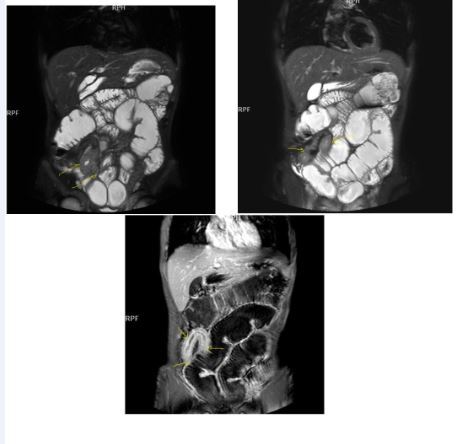

Chronic disease without active inflammation; Bowel wall thickening and enhancement on postgadolinium T1W images plus low signal intensity on T2W-FS images with possible stenosis and obstruction due to fibrosis, chronic disease with active inflammatoryexacerbations;these conditions can overlap with active inflammation, require longitudinal repeated scanning7, 12, 14, 20,26, 27, 28, 29, 30 (Figure 5a-b, Figure 6a-b)

Figure 5a.Enhancing bowel segments due to Crohn’s disease, on T1W post-contrast axial image, luminal enhancement is predominant, shown at 62 years old female with mild disease status.

Figure 5b.İrregular bowel wall and luminal enhancement of ileum, with loss of valvula conniventes on T1W coronal post-contrast sequence, seen on 26 years old male with moderate inflammatory bowel disease.

Figure 6a.Diffuse homogeneous contrast enhancement on the bowel wall and mucosa due to Crohn’s disease, seen at T1W post-contrast axial image, indicated at 23 years old male with mild disease status.

Figure 6b.Heterogeneous bowel wall and mucosa involvement with collaborating skip lesions, specific for Crohn’s disease, predominant in ileum and terminal ileum which are shown at T2W coronal sequence after OCA, regarded at 39 years old female with severe disease.